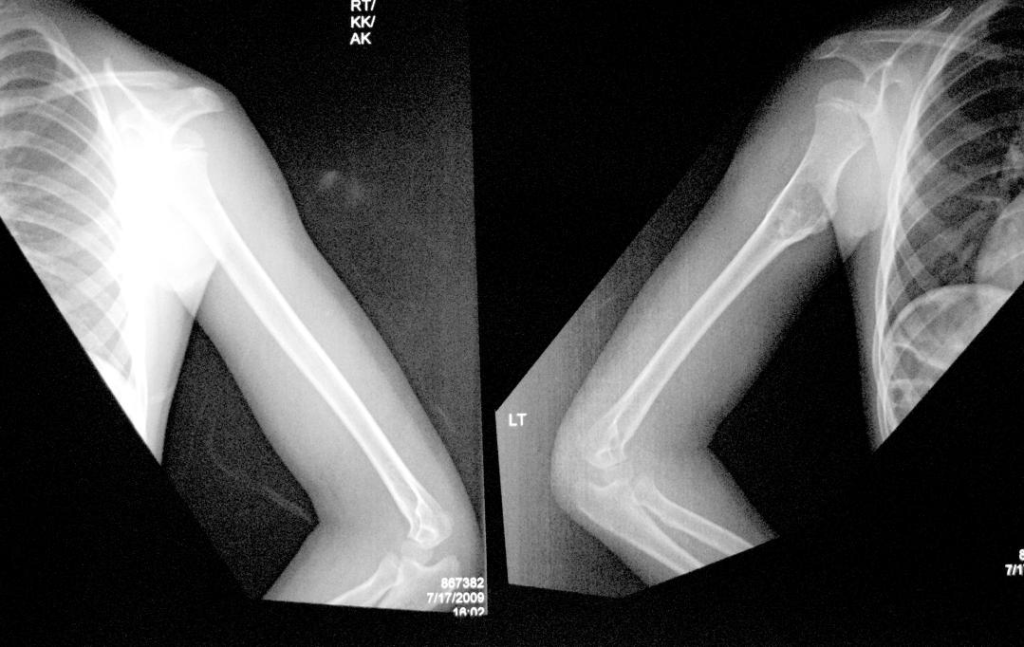

X-ray

Shows a bony swelling over upper third of the arm bone humerus of the left side Features BENIGN SESSILE tumour (non-pedunculated)

Osteochondroma upper third humerus of left side

AP view

Lateral view